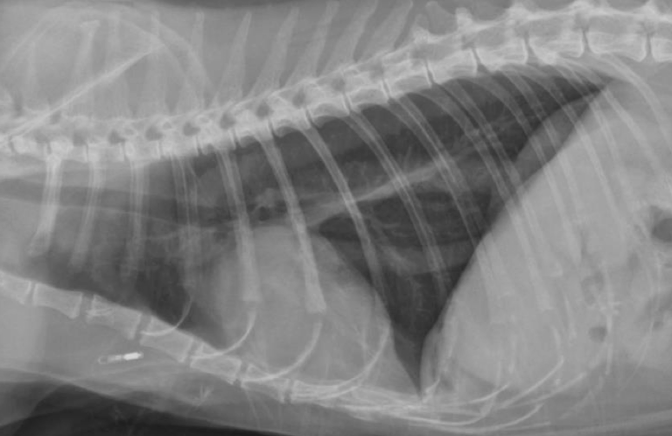

Normal esophagus